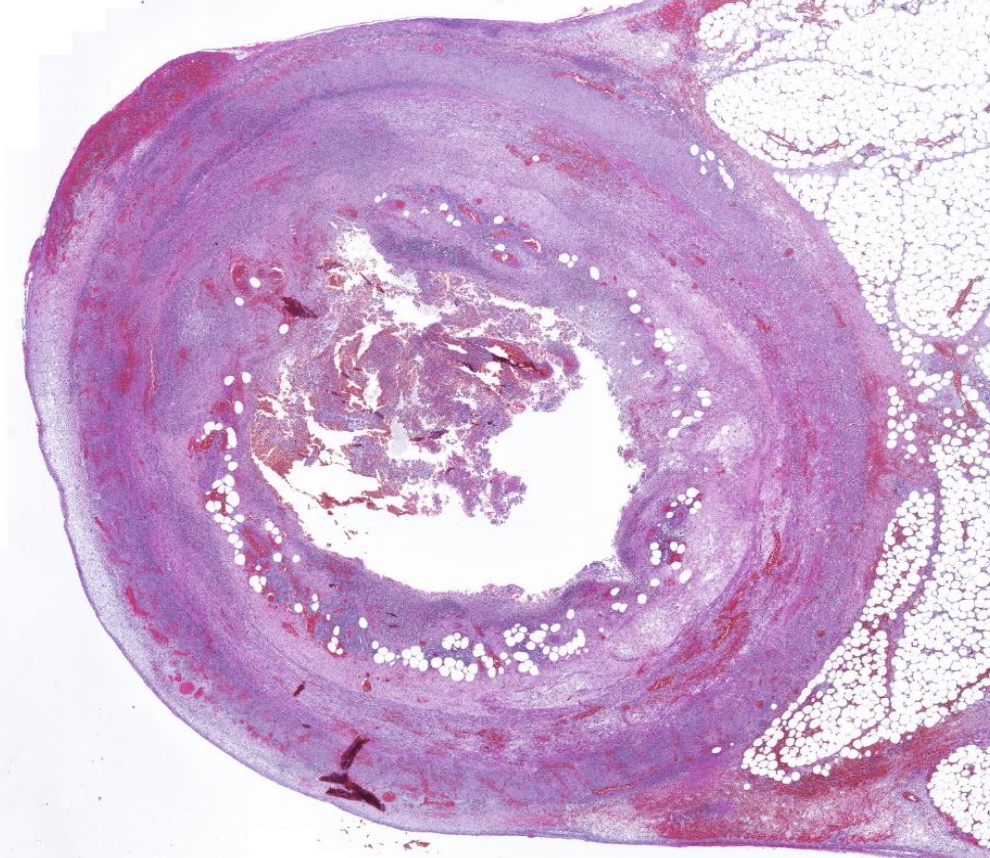

Diagnose?

Pleomorphes Speicheldrüsenadenom = BENIGNE

80% in der Parotis -> nicht destruktiv, nicht invasiv, nur verdrängend

v.a .Parotis, benigne, aufgebaut aus bindegewebiger Kapsel und epithelialen und mesenchymalen Gewebe (v.a. Knorpelgewebe)